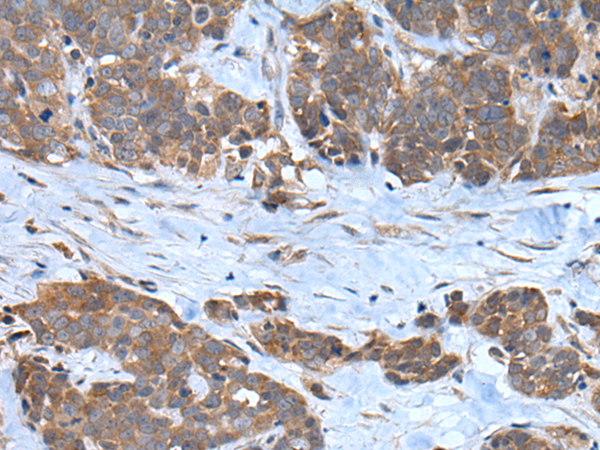

IHC positive control:

Human thyroid cancer and Human esophagus cancer

IHC Recommend dilution:

25-100